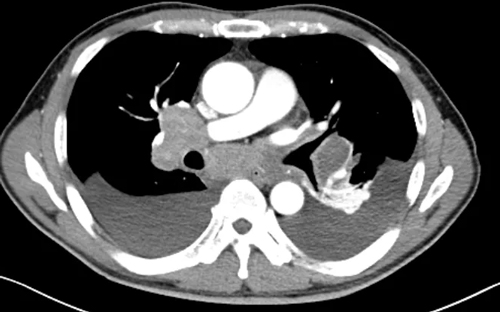

胸部CT顯示

雙側(cè)鎖骨上、下窩

雙側(cè)腋窩、縱隔內(nèi)及雙肺門區(qū)

多發(fā)軟組織結(jié)節(jié)

較大約“42×26×39mm”

脾大并多發(fā)低強化結(jié)節(jié)

考慮淋巴瘤

(化療前)